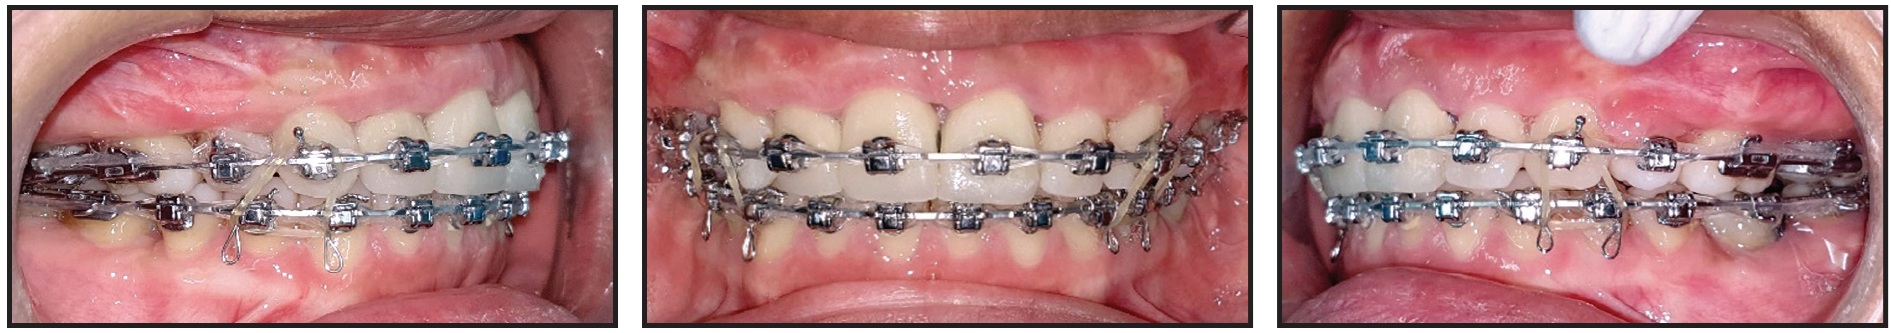

After six months of orthopedic treatment, the buccal and posterior arms of the h-RPE were removed, and the facemask was discontinued (Fig. 6).

Fig. 6 Buccal and posterior arms of h-RPE removed after six months of orthopedic treatment.

Primo** .022" labial brackets were bonded indirectly, and .014" nickel titanium archwires were inserted in both arches (Fig. 7). An open-coil spring was placed between the upper right lateral incisor and first premolar to provide space for eruption of the ectopic canine and to help center the upper dental midline.

Fig. 7 Primo** .022" labial brackets bonded and .014" nickel titanium archwires inserted in both arches; open-coil spring placed between upper right lateral incisor and first premolar to provide space for canine eruption and to center upper dental midline.

Two months later, when enough space had been created for the upper right canine, its eruption was initiated by tying an elastic module to its mesial bracket wings and to the archwire27 (Fig. 8).

After four months of canine alignment, an .019" × .025" nickel titanium archwire was inserted in the upper arch to continue leveling (Fig. 9). An .019" × .025" stainless steel archwire was inserted in the lower arch, with elastomeric chain added to close existing spaces and to prevent unwanted spaces from opening between the lower canines and lateral incisors. For sagittal and anterior vertical correction, the patient was asked to wear ³⁄16", 6oz Class III elastics*** 22 hours per day in a triangular configuration from hooks on the upper and lower canines to hooks on the upper first molars.

Fig. 8 Two months later, with sufficient space gained for upper right canine, eruption initiated with elastic module tied to mesial bracket wings and archwire.

Fig. 9 After four months of canine alignment, upper .019" × .025" nickel titanium and lower .019" × .025" stainless steel archwires inserted, with elastomeric chain added in lower arch for space closure.

Two months later, the brackets on the upper right central incisor and lower right first premolar were repositioned for finishing and detailing, and Class III elastics were applied asymmetrically to center the upper and lower dental midlines (Fig. 10).

Fig. 10 Two months later, brackets repositioned on upper right central incisor and lower right first premolar for finishing and detailing.